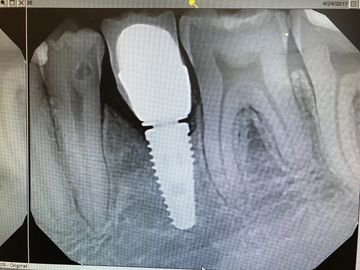

Send an X-ray to the LAB so they know where the implant is in relation to bone. This x-ray above shows the tussie measurement gauge finger tightened down on implant.

Tissue Measurement Gauge: In both surgical and restorative kits. The black lines indicate different tissue hieghts that match our healing abutment heights and the margins on our abutments.

the yellow lines on the xray indicate that both a 1.5 and 2.5 gignival margin on abutment would work for margin height selection of abutment.